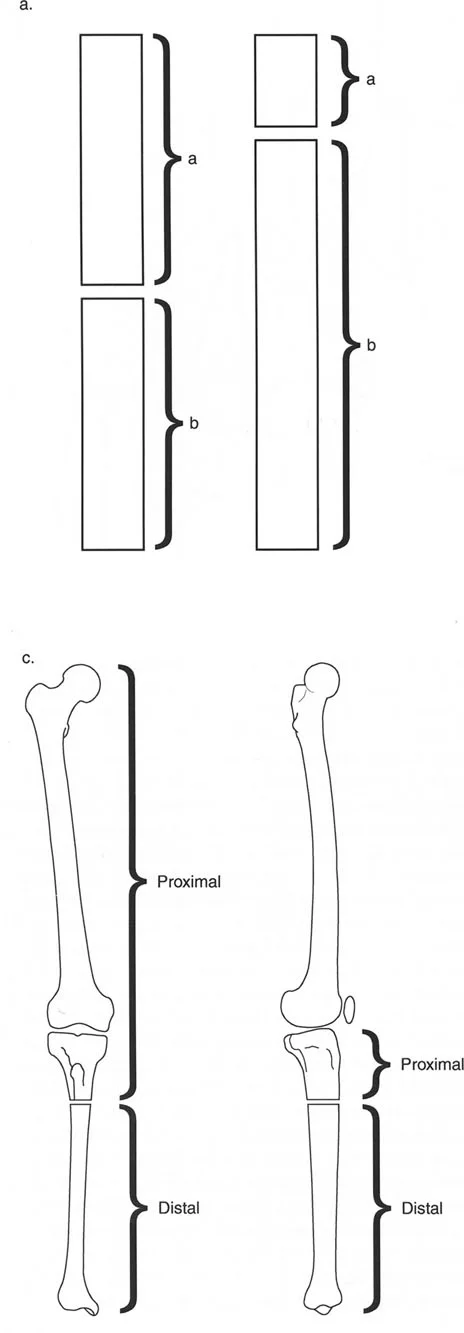

فهم المحور الميكانيكي للجسم

يعتمد جسم الإنسان على محاذاة دقيقة للمفاصل والعظام ليعمل بكفاءة. "المحور الميكانيكي" هو خط وهمي يمتد من مركز مفصل الورك إلى مركز مفصل الكاحل، ويمر عبر مركز مفصل الركبة. عند وجود تشوه، ينحرف هذا المحور، مما يضع ضغطًا غير طبيعي على المفاصل ويؤدي إلى الألم، وتآكل المفاصل المبكر (الخشونة)، وصعوبة في الحركة.

- الأشعة السينية الطويلة للطرفين (Long-leg Standing X-rays): هذه الأشعة ضرورية لتقييم المحور الميكانيكي للطرف بالكامل أثناء الوقوف. تسمح بتحديد مركز دوران الانحراف (CORA) بدقة، وهو النقطة التي يجب أن تتمحور حولها عملية التصحيح.

القياسات الهندسية:

- باستخدام صور الأشعة السينية الطويلة، يقوم الأستاذ الدكتور محمد هطيف بإجراء قياسات هندسية دقيقة لتحديد الزوايا غير الطبيعية (مثل mLDFA و MPTA)، ومقدار القصر، ودرجة الدوران، وأي انحرافات في المحور الميكانيكي. هذه القياسات هي الأساس لتخطيط الجراحة بدقة متناهية.

- قاعدة قطع العظم 1: عندما يمر قطع العظم ومحور تصحيح الانحراف (ACA) كلاهما عبر مركز دوران الانحراف (CORA)، فإن نهايات العظم ستنحرف دون ترجمة (انزياح). يتم استعادة المحور الميكانيكي، وتظل نهايات العظم متقاربة تمامًا، مما يخلق تصحيحًا كلاسيكيًا "إسفينيًا مفتوحًا" أو "إسفينيًا مغلقًا".

- قاعدة قطع العظم 2: عندما يمر محور تصحيح الانحراف (ACA) عبر مركز دوران الانحراف (CORA)، ولكن يتم إجراء قطع العظم على مستوى مختلف (غالبًا بسبب ضعف جودة العظم عند CORA أو مشاكل في الجلد)، فإن نهايات العظم ستنحرف وتخضع لترجمة محسوبة ومقصودة لإعادة محاذاة المحور الميكانيكي.

- قاعدة قطع العظم 3: (للاكمال) عندما يمر قطع العظم عبر مركز دوران الانحراف (CORA)، ولكن يتم وضع محور تصحيح الانحراف (ACA) خارج CORA، سيتم إنشاء تشوه ترجمة جديد، وهو خطأ شائع في وضع المفصلات غير المخطط له جيدًا.